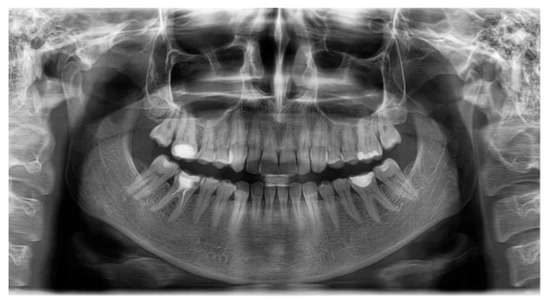

| SNA | 80.03 | 81.08 | 3.7 | Normal A-P position of the maxilla |

| SNB | 75.40 | 79.17 | 3.8 | Normal A-P position of the mandible |

| ANB | 2.46 | 4.63 | 1.8 | skeletal class II |

| FMA | 26.32 | 29.63 | 3.0 | Hypodivergent facial pattern |

| Gonial angle | 123.44 | 124.31 | 5.4 | Normal gonial angle |

| APDI | 74.22 | 85.74 | 4.0 | Skeletal class II |

| A to N-Perp (FH) | −2.58 | 0.4 | 2.3 | Retruded maxilla |

| B to N-Perp (FH) | −12.06 | −3.5 | 2.0 | Retruded mandible |

| Pog to N-Perp (FH) | −9.14 | −1.8 | 2.5 | Retruded chin point |

| FH to AB | 76.26 | 81 | 3.0 | Skeletal class II |

| A-B to mandibular plane | 77.41 | 69.3 | 2.5 | Large angle |

| Wits appraisal | 5.61 | −2.74 | 0.3 | Skeletal class II |

| Overjet | 4.79 | 2 | 2.0 | Large overjet |

| Overbite | 2.46 | 2 | 2.0 | Normal overbite |

| U1 to FH | 100.88 | 113.8 | 6.4 | Retroclined upper incisor |

| U1 to SN | 93.59 | 105.28 | 6.6 | Retroclined upper incisor |

| U1 to UOP | 70.28 | 55 | 4.0 | Retroclined upper incisor |

| IMPA | 80.50 | 91.62 | 3.2 | Retroclined lower incisor |

| L1 to LOP | 74.77 | 66 | 5.0 | Retroclined lower incisor |

| Interincisal angle | 152.29 | 128 | 5.3 | Uprighted interincisal angle |

| Cant of occlusal plane | 5.66 | 9.3 | 3.8 | Normal occlusal plane angle |

| U1 to NA(mm) | 0.10 | 4 | 3.0 | Retruded upper incisor |

| U1 to NA(deg) | 13.55 | 22 | 5.0 | Retroclined upper incisor |

| L1 to NB(mm) | 1.5 | 4 | 2.0 | Retruded lower incisor |

| L1 to NB(deg) | 9.52 | 25 | 5.0 | Retroclined lower incisor |

| Upper incisal display | 3.17 | 2.5 | 1.5 | Normal incisal display |

| Upper lip to E-plane | −3.42 | 0 | 2.0 | Retruded upper lip |

| Lower lip to E-plane | −2.22 | 0 | 2.0 | Retruded lower lip |

| Nasolabial angle | 114.84 | 95 | 5.0 | Retruded lip |

| Extraction Index | 159.69 | 153.8 | 7.8 | Normal |